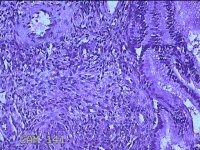

宫颈赘生物

性别

女

年龄

38岁

临床诊断

稽留流产

一般病史

停经2月余,阴道流血5天。

标本名称

大体所见

灰白粉红色不规则肿物1.5x1.2x0.3cm两个,表面糜烂,切开肿物呈实性,切面灰白粉红色,质软。

有可能调整一下拍照,部分区域看不清